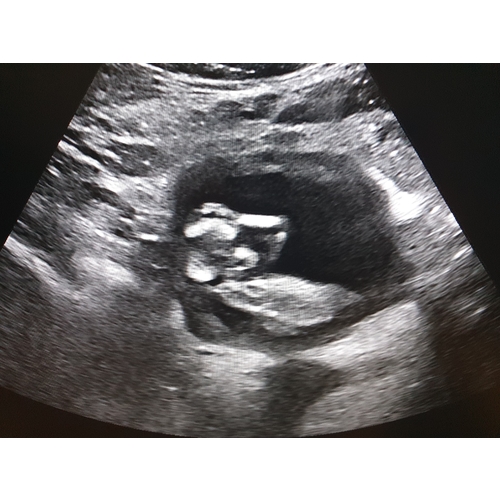

Gezichtje vanaf de voorkant. Was net zo'n porseleine horror pop😅

Ik moest even goed kijken, maar ik zie het ja! Inderdaad griezelig zo